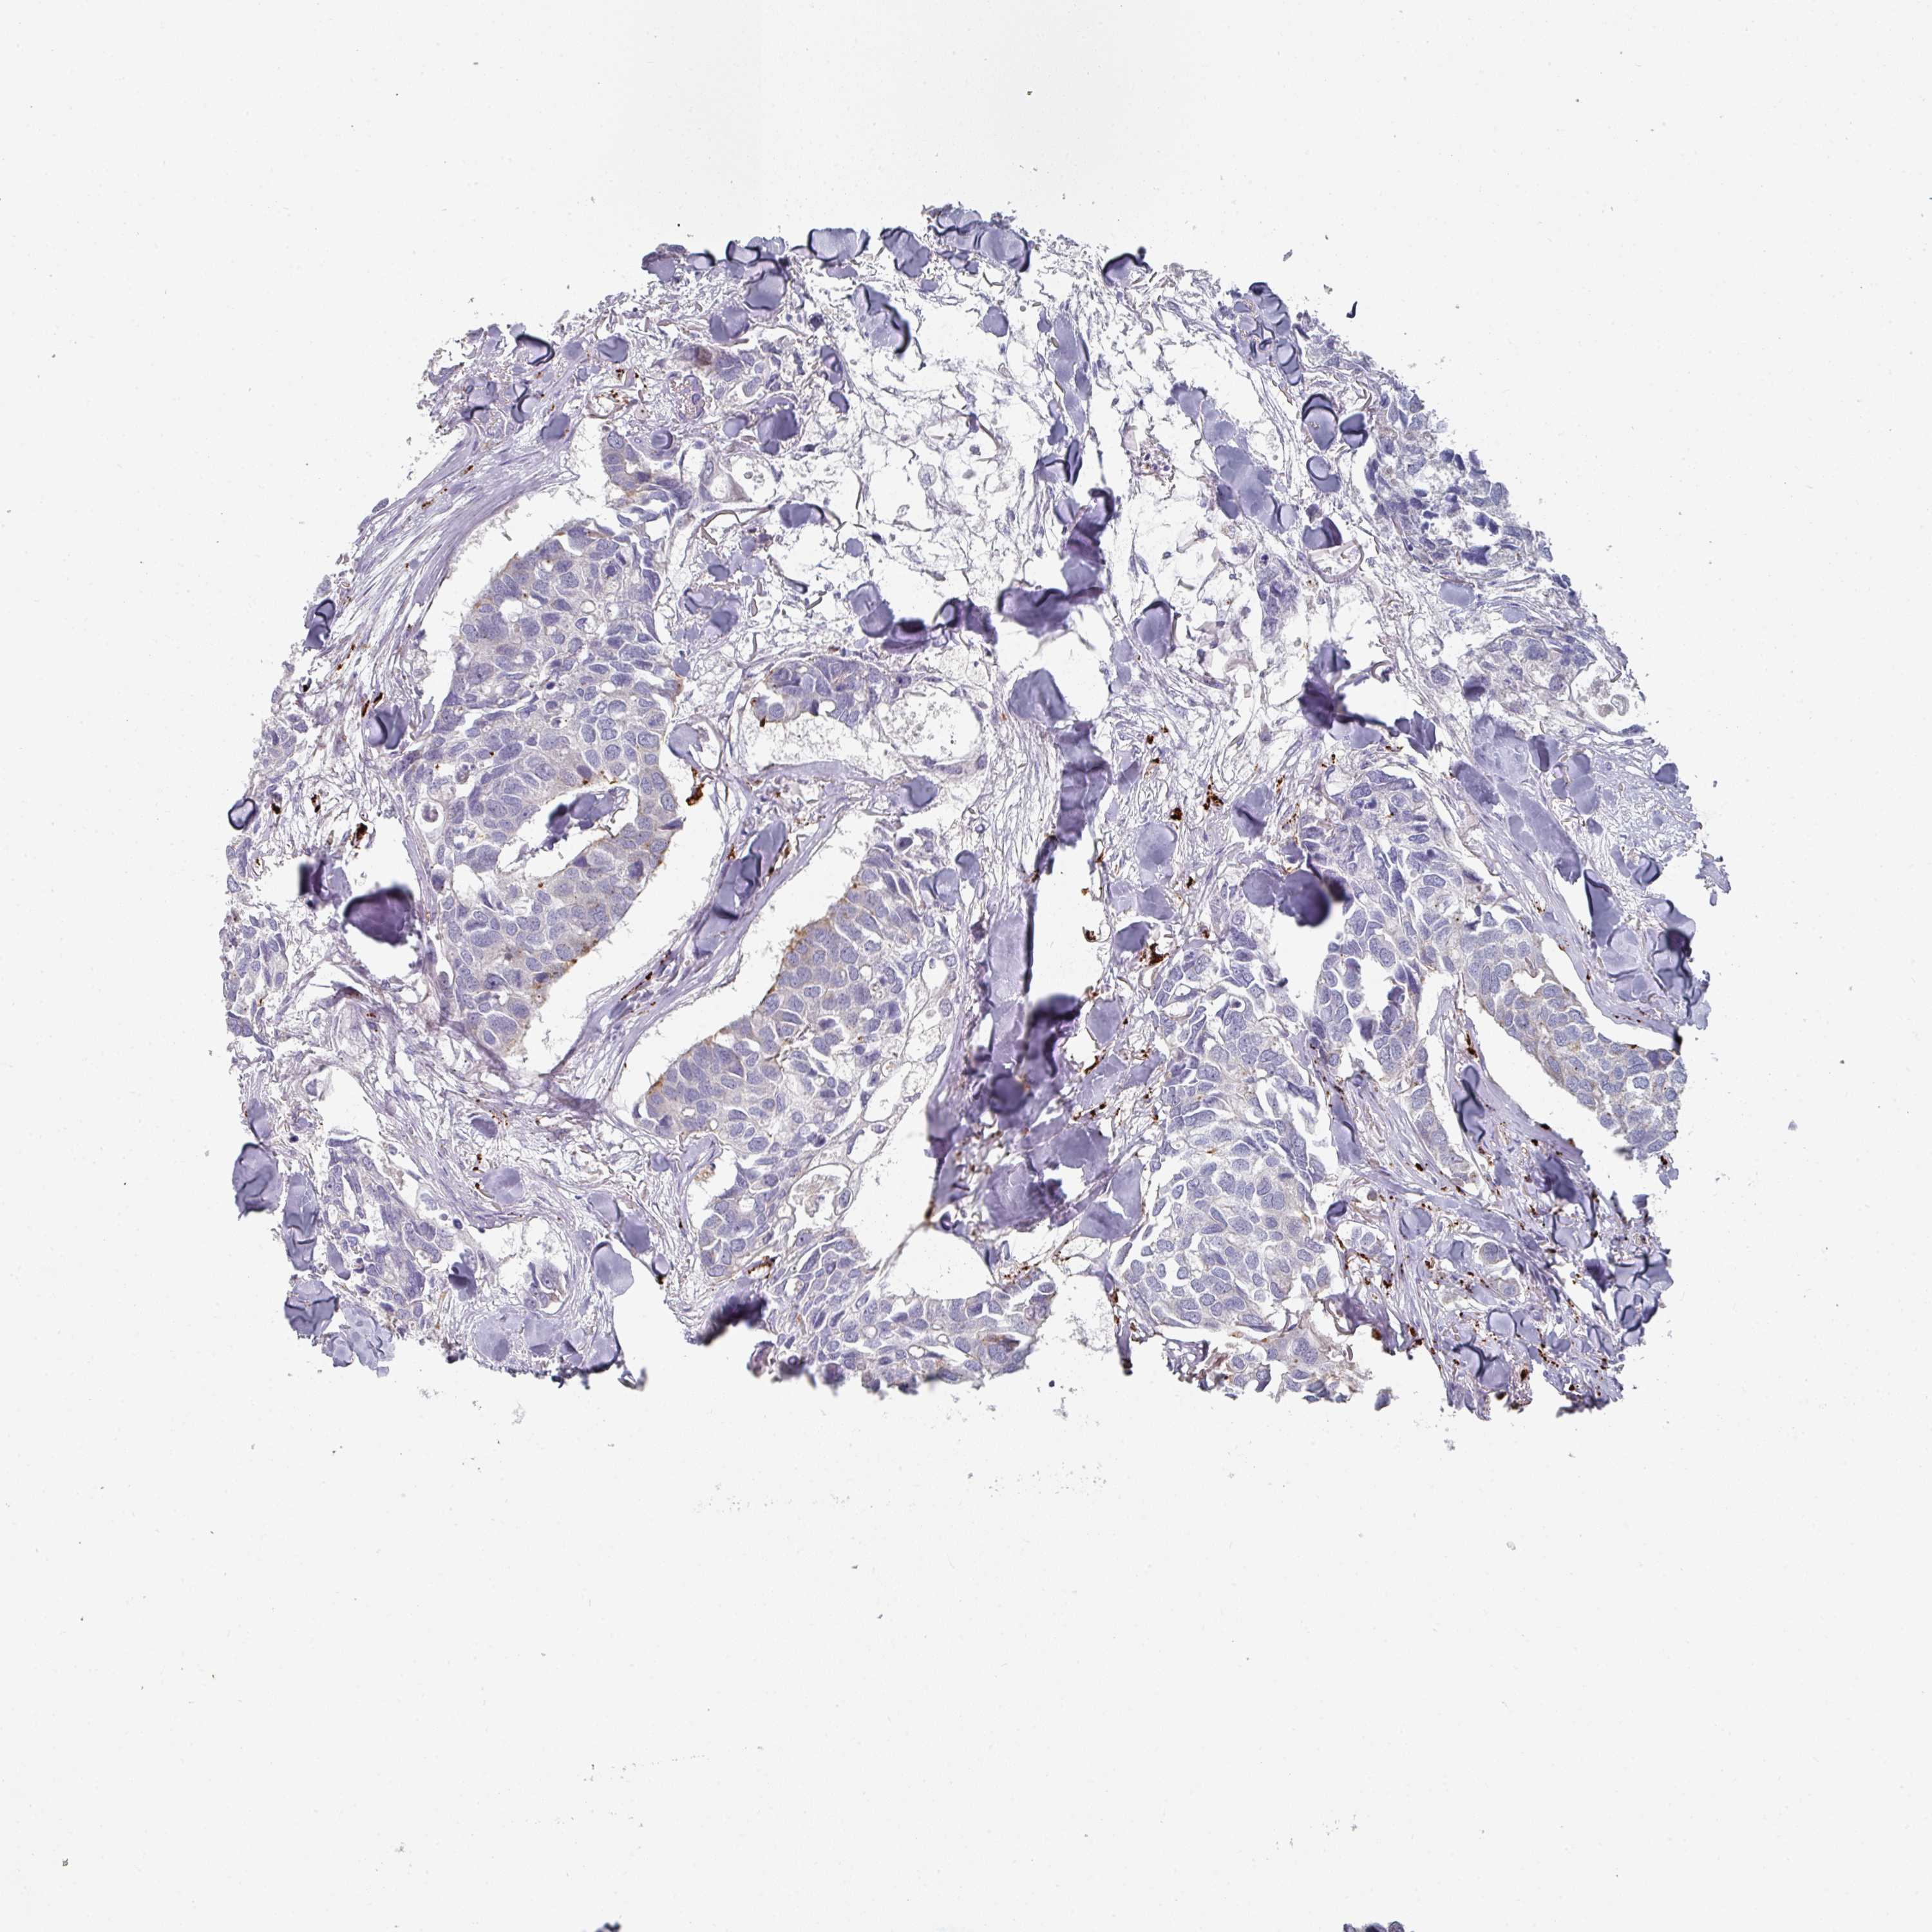

CANCER BREAST CANCER Show tissue menu

BRCA TCGA BRCA VALIDATION PROTEIN EXPRESSION